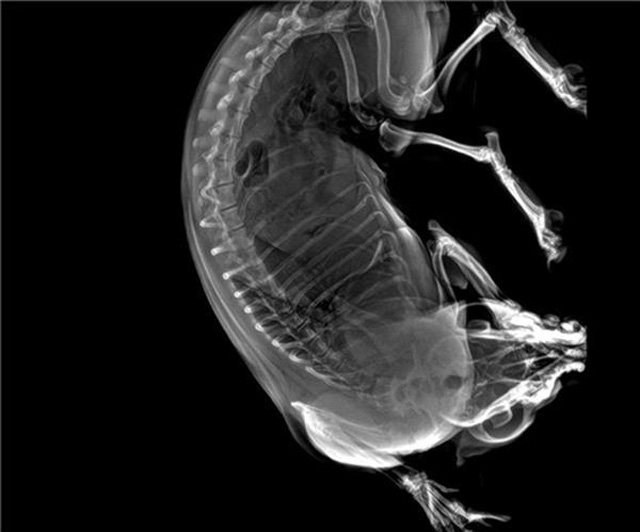

寵物DR的工作原理是X光線穿透動物體后在屏幕或者膠片上面顯示體內影像。輔助寵物醫(yī)生讀片跟準確的治療,寵物DR顯示是寵物醫(yī)院診所的配置,提高了診斷的效率。DR的檢測效率比X線高44%,成像快采集時間10MS以下。3秒左右就可以看到檢查圖像。常規(guī)的胸部DR還要幾分鐘。所以寵物DR的出片速度是非??斓摹:芨叩目臻g分辨率低噪音。可以獲得高清圖像,提高檢測正確率避免誤診等等問題。數(shù)字化圖像的優(yōu)勢是可以保留原始數(shù)據(jù),圖片識別,二三維的重建,醫(yī)學影像學實現(xiàn)全數(shù)字化和無膠片化鋪平了道路。提供照片打印服務,防止照片丟失而重復照片。有針對性的對圖像進行處理,以提高診斷率。寵物DR的輻射量很低的,對人體的輻射風險不大。